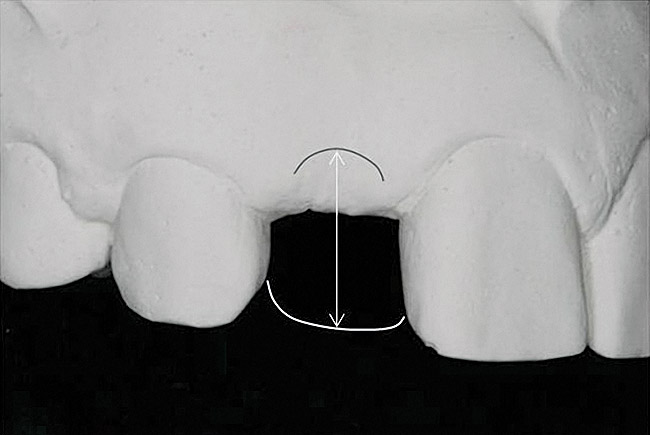

Figure 7  These images summarize the various dimensional assessments that underscore the Rules of Six guidelines, which enable simple planning for uncomplicated single-tooth dental implant therapy: Finding mesiodistal or inter-radicular (Fig 7), buccolingual (Fig 8), and inter-occlusal (Fig 9) distances of 6 mm can assure uncomplicated implant placement and restoration.

Figure 7

Figure 8  These images summarize the various dimensional assessments that underscore the Rules of Six guidelines, which enable simple planning for uncomplicated single-tooth dental implant therapy: Finding mesiodistal or inter-radicular (Fig 7), buccolingual (Fig 8), and inter-occlusal (Fig 9) distances of 6 mm can assure uncomplicated implant placement and restoration.

Figure 8

Figure 9: These images summarize the various dimensional assessments that underscore the Rules of Six guidelines, which enable simple planning for uncomplicated single-tooth dental implant therapy: Finding mesiodistal or inter-radicular (Fig 7), buccolingual (Fig 8), and inter-occlusal (Fig 9) distances of 6 mm can assure uncomplicated implant placement and restoration.

Figure 9